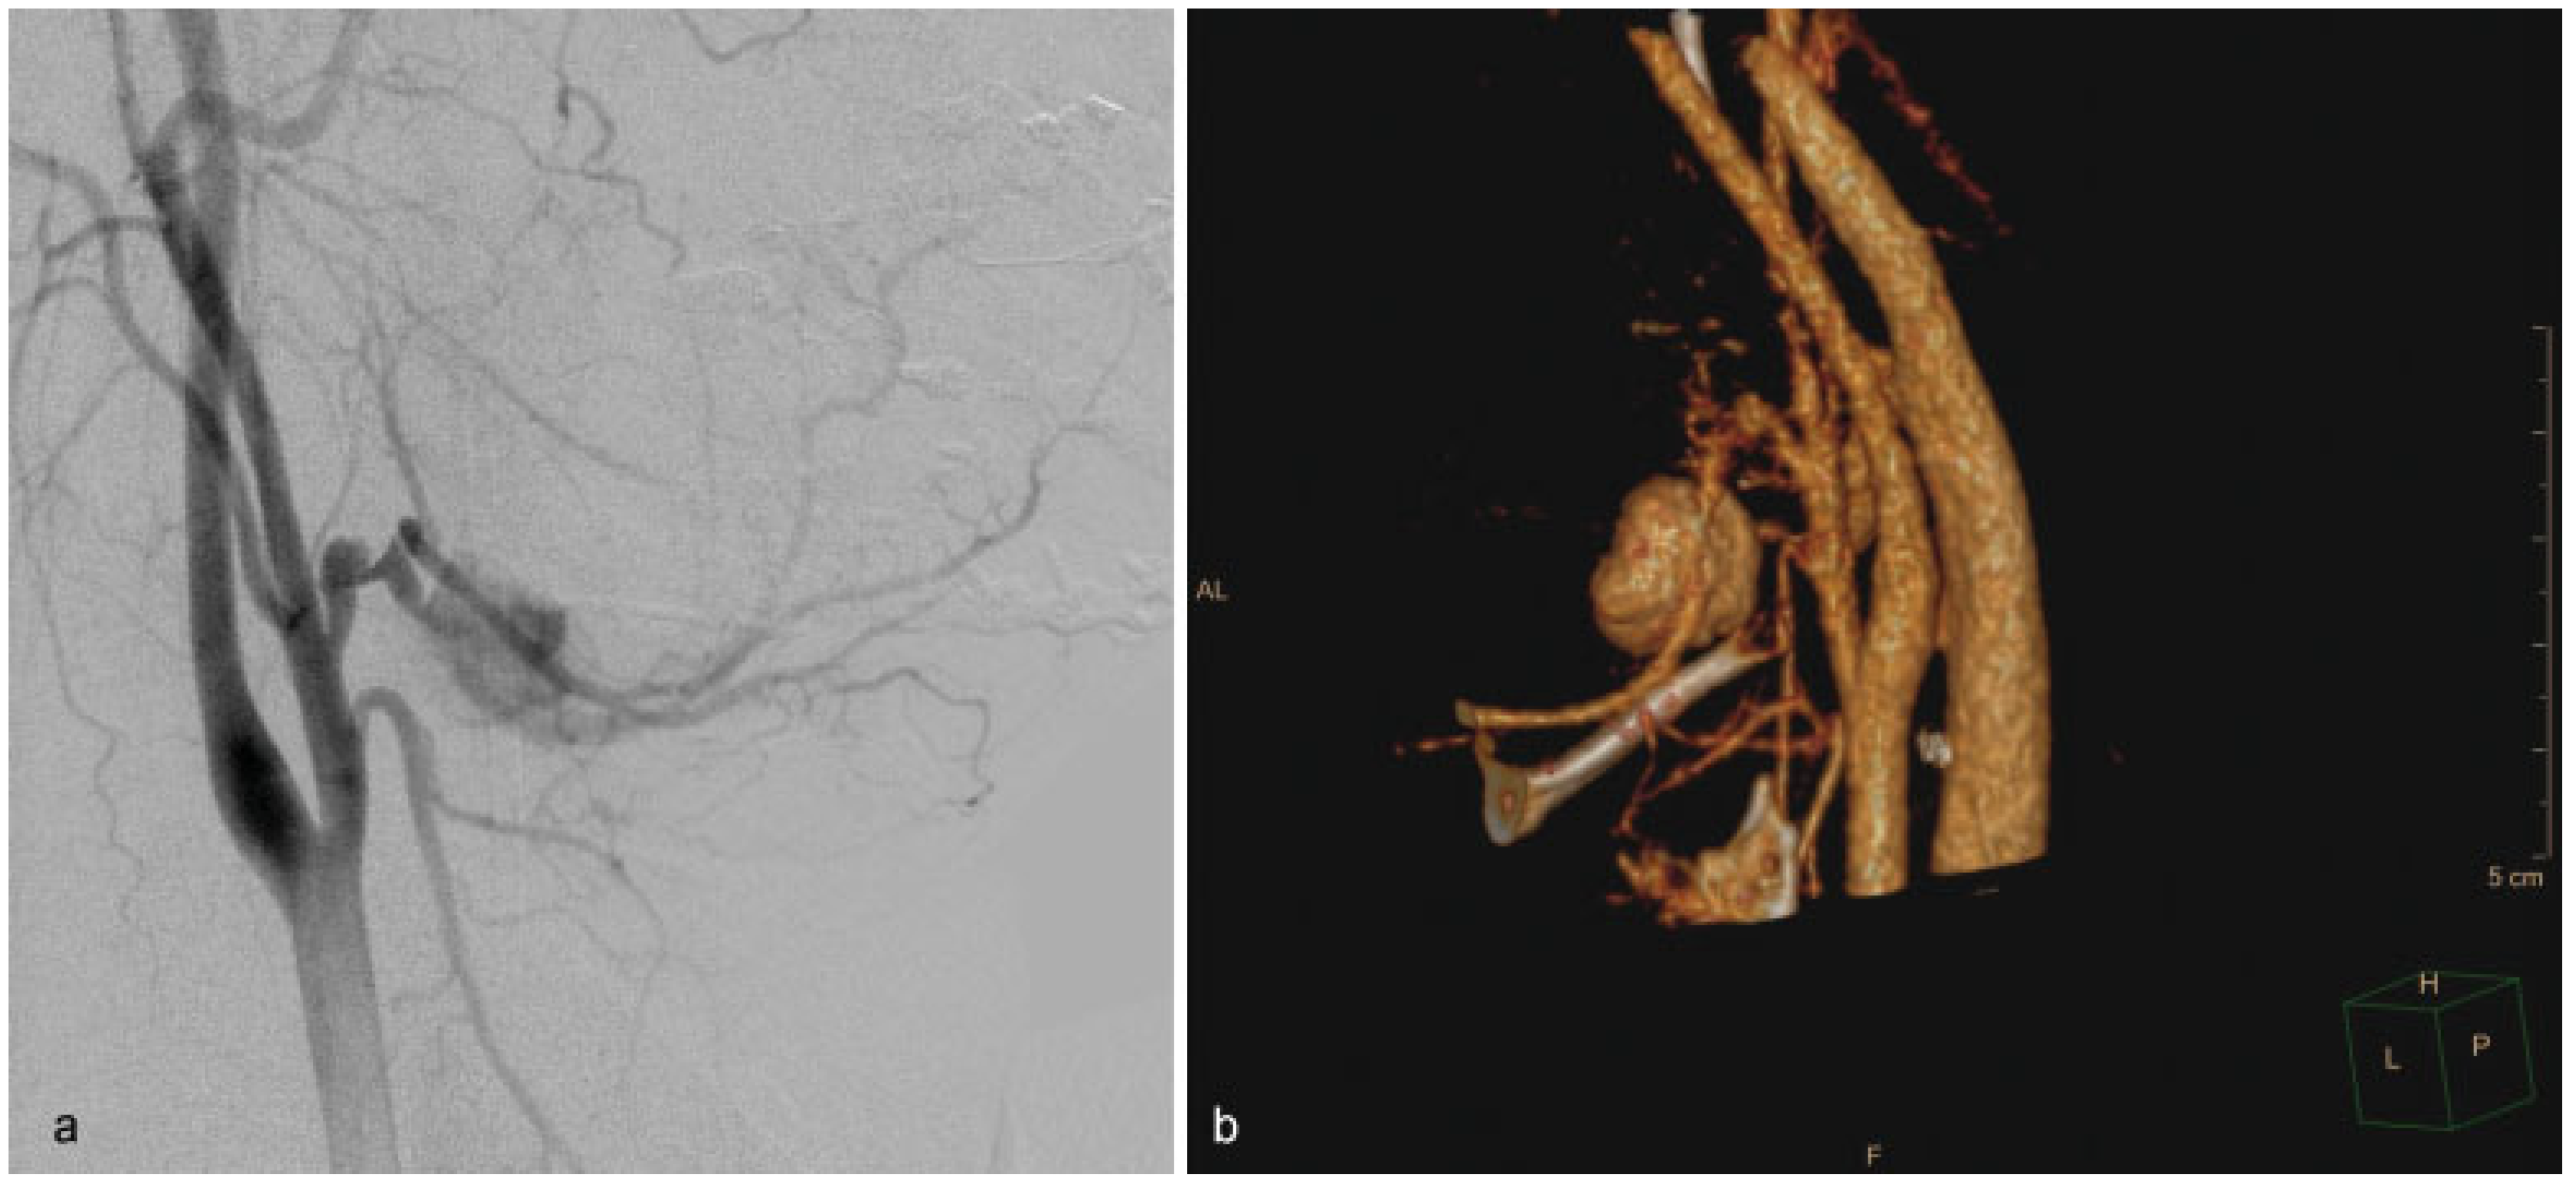

Figure 2), which was superselectively embolized with coils by the interventional radiologist (

Figure 3). The patient was stabilized and was discharged from hospital 3 weeks later (

Figure 4).

Final angiographic controls showed complete occlusion of the pseudoaneurysm without immediate complications. The following postoperative period elapsed uneventfully.